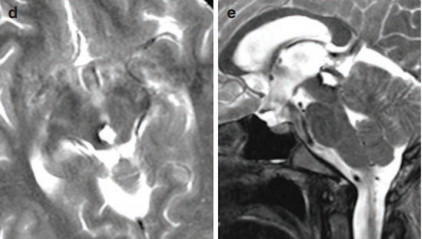

術(shù)后MRI顯示該血管畸形被完全切除(d和e)。